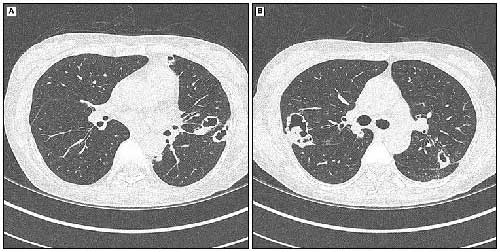

间质性肺疾病的组织病理学分类包括非特异性间质性肺炎(NSIP),普通间质性肺炎(UIP),隐缘性机化性肺炎(COP),淋巴细胞间质性肺炎(LIP),急性间质性肺炎(AIP)/弥漫性肺泡损伤 (DAD),呼吸性细支气管炎相关间质性肺疾病(RB-ILD)及较为罕见的脱屑性间质性肺炎(DIP)。在风湿性疾病患者中,普通型间质性肺炎预后最差,患者的5年死亡率>50%。

风湿性疾病肺受累常见影像学表现

非特异性

普通

急性间质性

淋巴细胞间质性

脱屑性

COP

类风湿结节